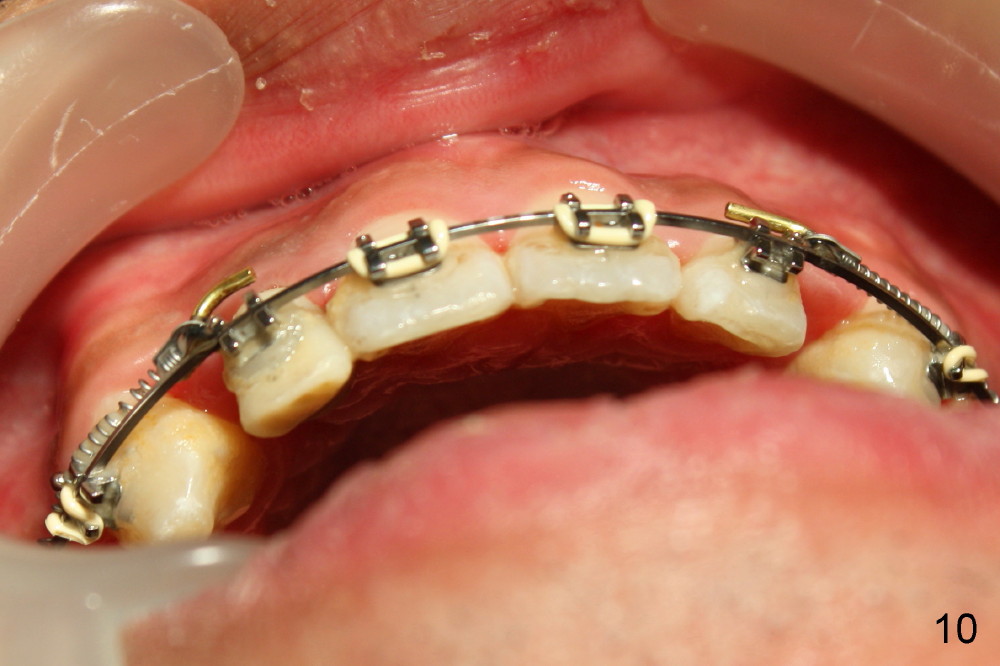

The patient returns 1 month post distalization of the upper incisors (Fig.10-12, 9 months of treatment). Bilateral canine relationship is Class I (Fig.11,12). All needs to be done is to continue distalizing the upper incisors or slightly mesialize the canines if indicated.

Fig.13-15 shows the upper incisors totally 4.5 month of retraction. The upper left canine (Fig.15: #11) seems to be distalized too much, as compared to the dashed line. Therefore whole arch power chain is placed with an intention to bring the canine mesially (arrowhead) while continue distalizing the incisors (including #10 (arrowhead).